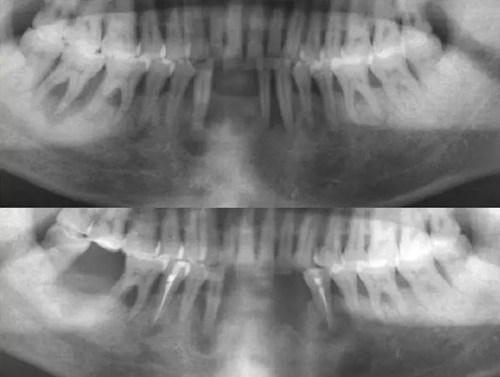

4.通過(guò)X線(xiàn)片對(duì)根管系統(tǒng)進(jìn)行預(yù)測(cè)

通過(guò)X線(xiàn)片對(duì)根管系統(tǒng)進(jìn)行預(yù)測(cè):確定根管的彎曲度、根管的數(shù)目、根尖彎曲的走向,是否有外吸收、內(nèi)吸收、根裂等情況出現(xiàn),這將對(duì)治療方案的確定有很大幫助。